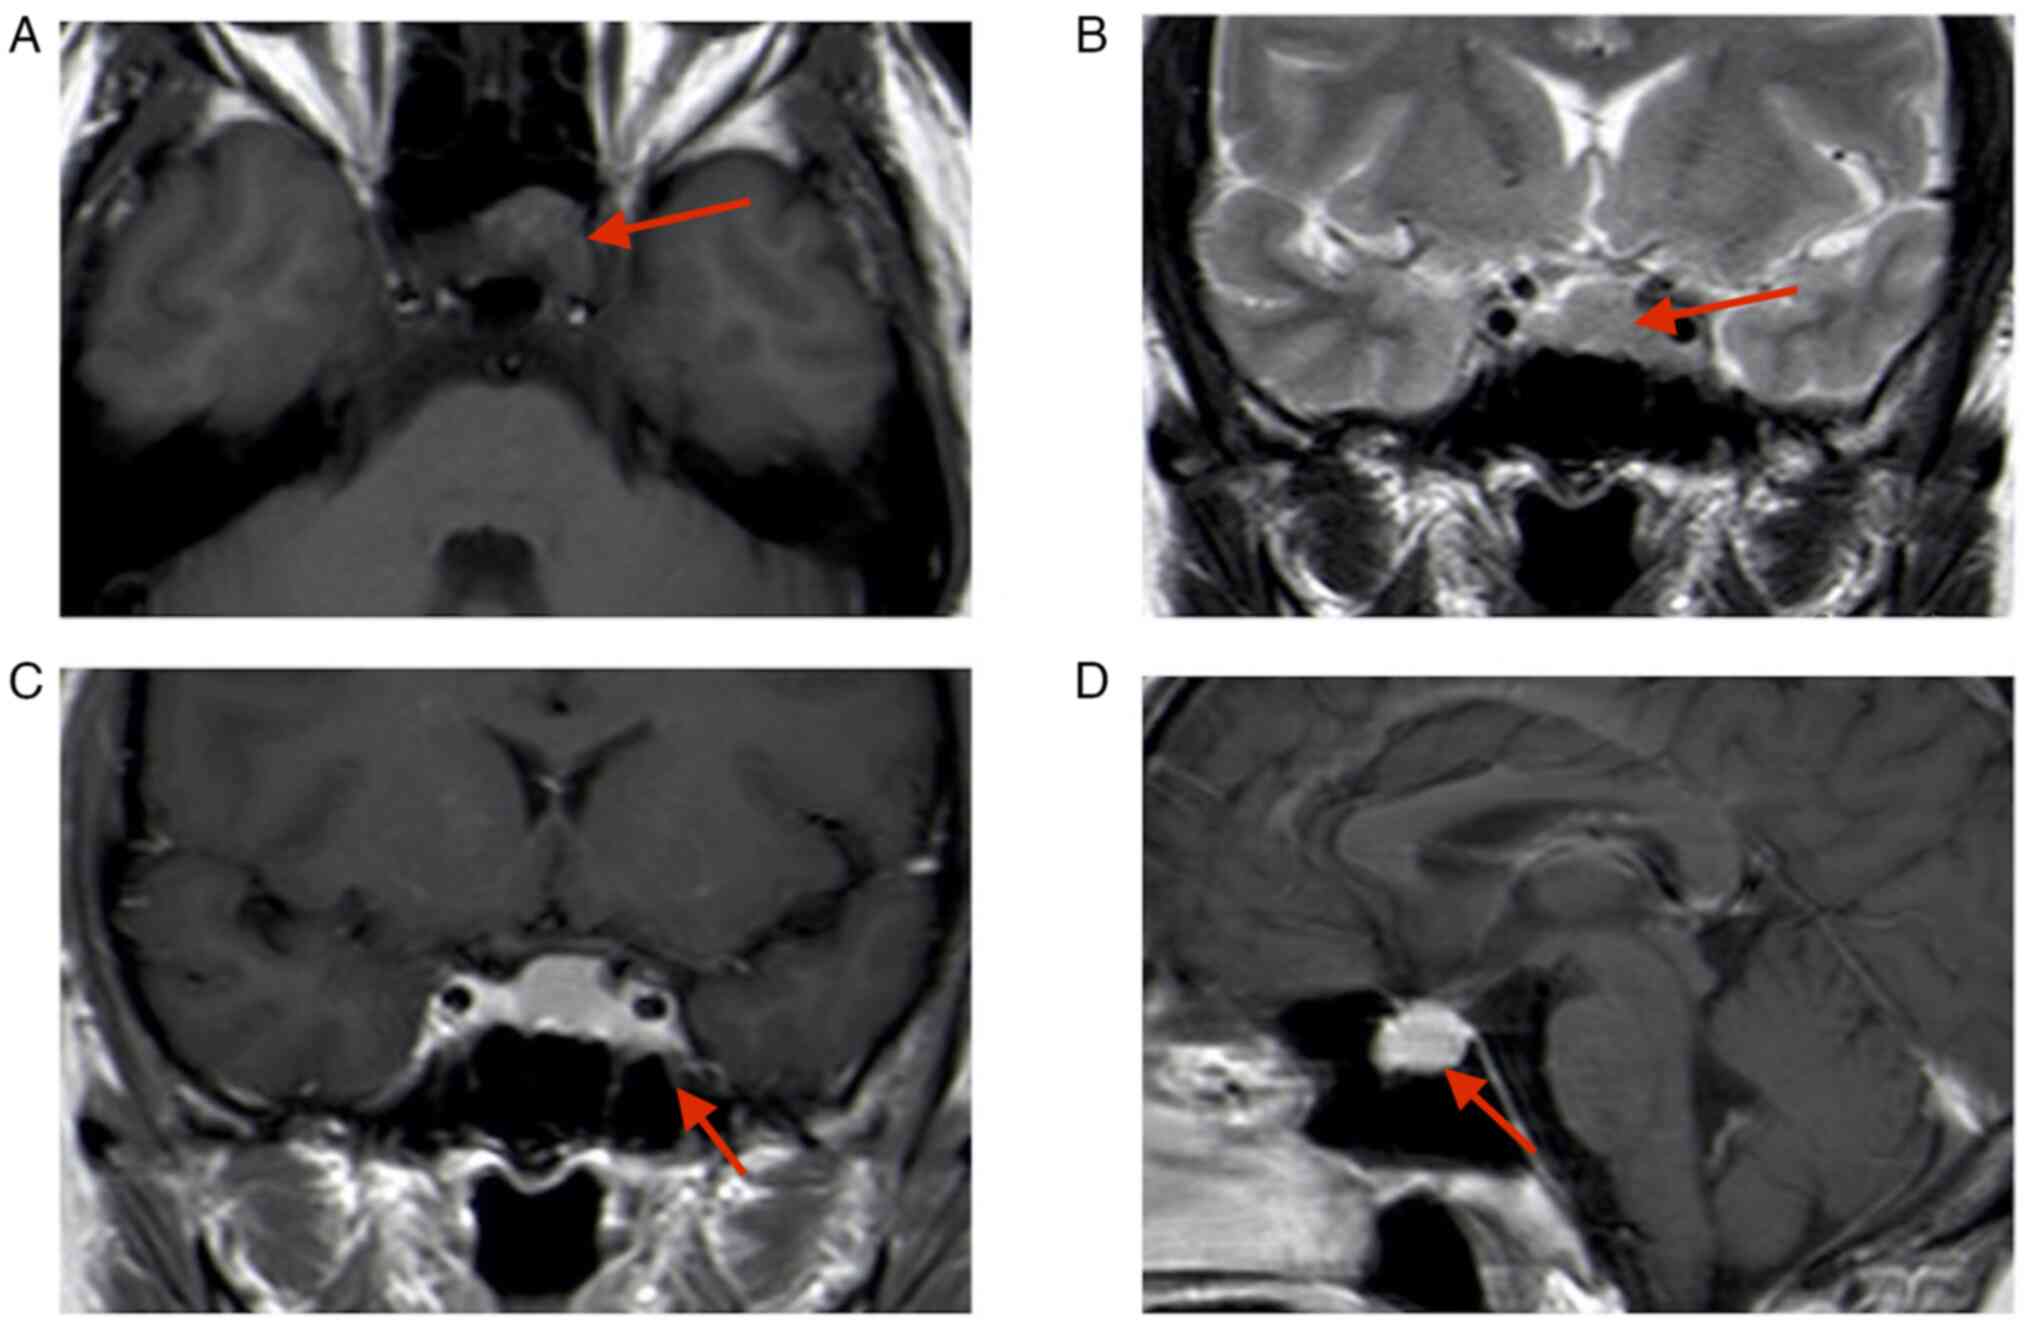

A 43-year-old female patient presented at the Department of Neurosurgery of the Affiliated Suzhou Hospital of Nanjing Medical University (Suzhou, China) three months following a microscopic transsphenoidal saddle area tumor partial resection at a different hospital (January 2022). The patient reported blurred vision in the left eye. The nervous system examination indicated normal eye function. The first magnetic resonance imaging (MRI) performed at the external hospital (October 2021) indicated the presence of a solid tumor sized 20×18×15 mm in the pituitary fossa; this was confirmed by an isodense signal on T1-weighted imaging and T2-weighted imaging (Fig. 1). Enhanced MRI indicated enhancement of the mass and displacement of the pituitary gland to the upper right side. Due to the similar imaging feature to a pituitary tumor, the lesion had been misdiagnosed as a pituitary tumor prior to the first surgery. Subsequently, the patient received a microscopic transsphenoidal saddle area tumor resection; however, only part of the tumor was removed due to the rich blood supply of the tumor and its proximity to the cavernous sinus; intraoperative bleeding from the cavernous sinus was apparent, making it impossible to completely resect the tumor.

Figure 1.

Initial MRI performed at the external hospital (October 2021). (A) T1-MRI; (B) T2-MRI; (C) enhanced T1-MRI coronal image; lesion size, 20×18×15 mm (red arrows indicate lesion areas); (D) enhanced T1-MRI sagittal image. Red arrows indicate lesion areas.